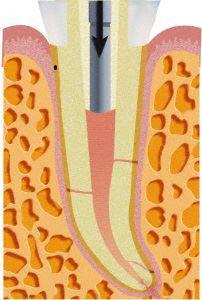

Danach werden die Wurzelkanäle mit bioverträglichen Materialien mit Hilfe von zeit- und materialaufwändigen Kondensationsverfahren gefüllt.

Für einen langfristigen Erfolg ist jedoch entscheidend, dass die Zahnkrone bei kleinen Defekten adhäsiv restauriert wird und bei großen Defekten häufig mit einem Stiftaufbau und Zahnersatz versehen wird.